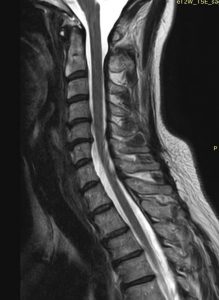

Ο απεικονιστικός έλεγχος με μαγνητική και αξονική τομογραφία της σπονδυλικής στήλης ανέδειξε εικόνα δισκοκήλης στα επίπεδα Α5/6 και λιγότερο Α4/5. Το σημαντικότερο εύρημα ήταν η πλάγια τρηματική στένωση με πίεση επί των ριζών Α6 & Α5 αριστερά.

Διενεργήθηκε πρόσθια δισκεκτομή και αποσυμπίεση των ριζών στα επίπεδα Α4/5 & Α5/6